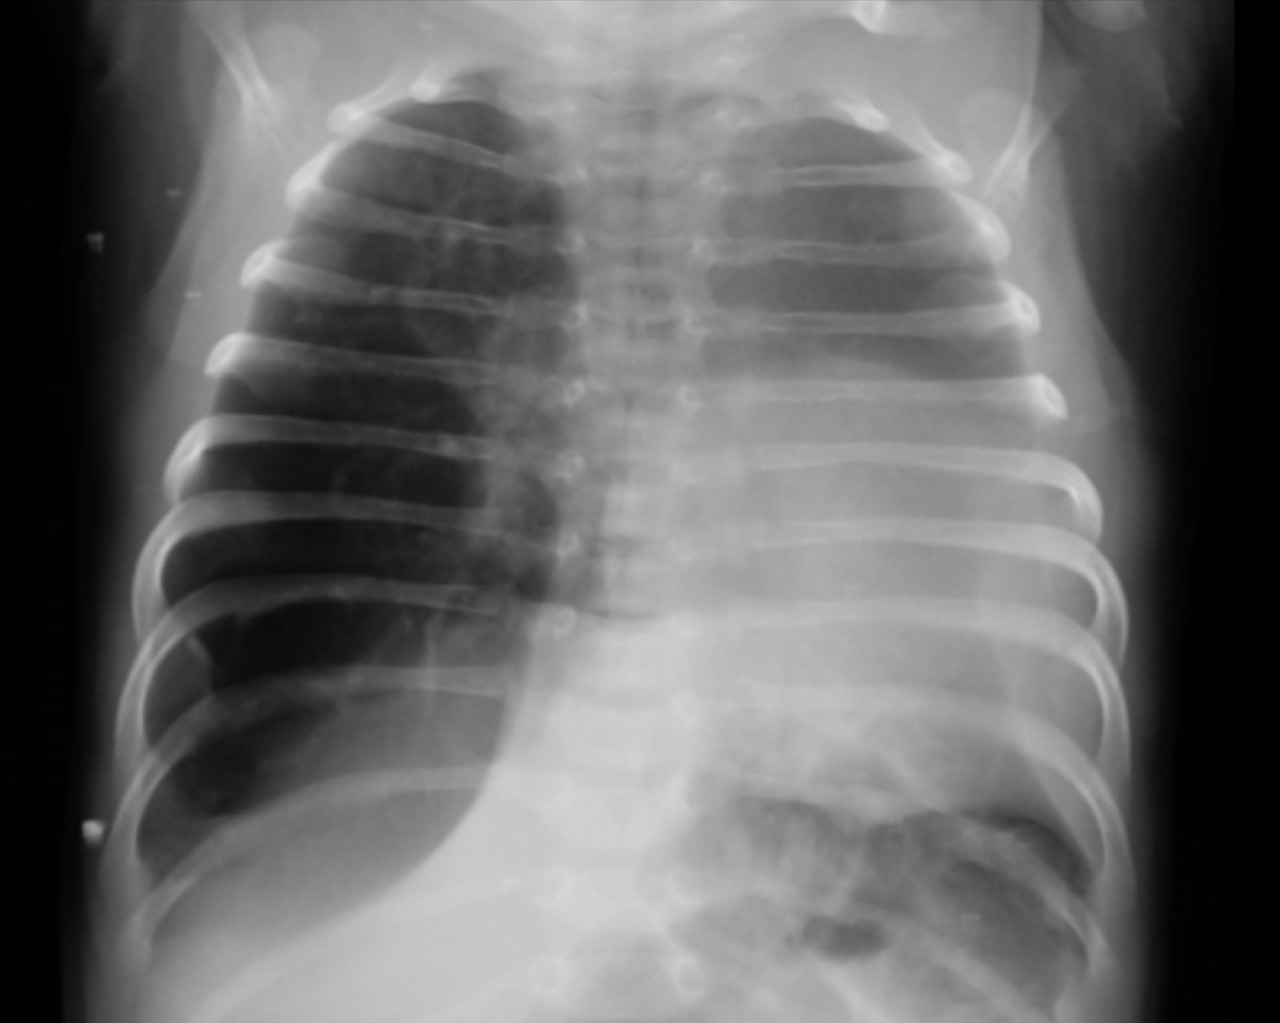

Un nouveau-né âgé de 1 mois est admis aux urgences pédiatriques pour prise en charge d’une détresse respiratoire. Le début de la symptomatologie remonte à la naissance, par l’installation d’une polypnée s’aggravant lors des cris et de l’alimentation, associée à des épisodes de toux sèche. L’examen clinique trouve un nouveau-né tachypnéique, cyanosé avec tirage intercostal et bombement de l’hémithorax droit associé à un wheezing auscultatoire et une SaO2 à 90 % à l’air ambiant. Le patient est mis sous oxygénothérapie et une radiographie thoracique est réalisée, objectivant une hyperaération de l’hémichamp pulmonaire droit refoulant le médiastin (fig. 1). Un scanner est effectué sans injection de produit de contraste et sans sédation, montrant une hyperclarté hypovasculaire avec une expansion du lobe supérieur gauche, refoulant le médiastin et la trachée à gauche, associée à une atélectasie du lobe inférieur droit et de l’hémichamp pulmonaire controlatéral (fig. 2). L’ensemble des éléments radio-cliniques plaident en faveur d’un emphysème lobaire géant compressif congénital (ELGC). Une lobectomie supérieure droite est réalisée, avec une bonne évolution clinique.

En période post-natale, le diag­nostic est plus facile. Sur la radiographie thoracique, le lobe atteint est distendu et hyperaéré, avec une fine trame vasculaire, élément sémiologique essentiel pour différencier un emphysème lobaire géant d’un pneumothorax. Le médiastin est refoulé vers le côté controlatéral et le lobe adjacent est comprimé.5